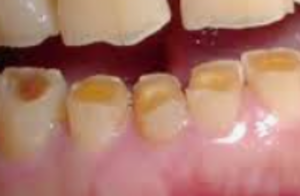

楔上欠損

咬耗